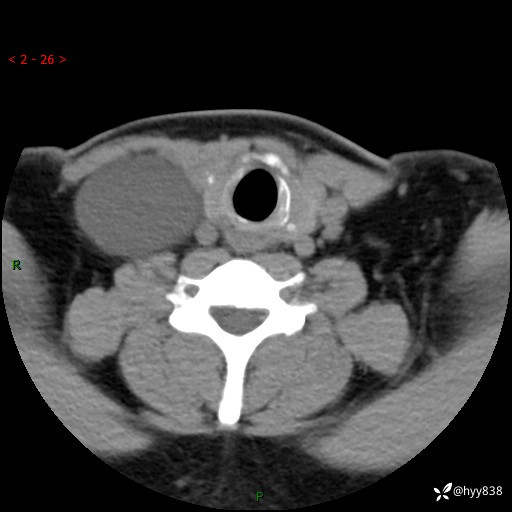

颈部CT平扫+增强